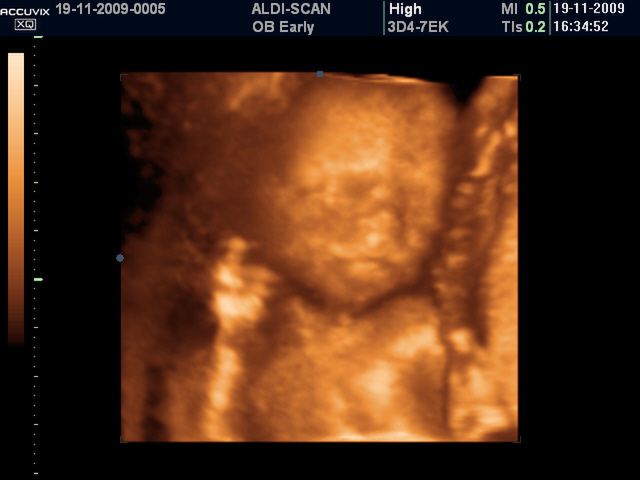

/ 3Płód w 11 tygodniu ciąży - linie papilarne

Na palcach dzieka pojawiają się paznokcie natomiast na opuszkach linie papilarne